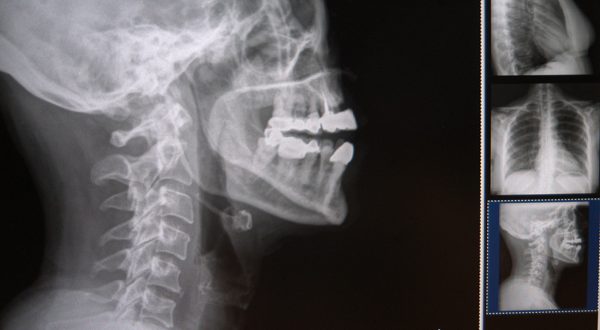

Explicó que la columna cervical se sitúa en el cuello, su función es contener y proteger la médula espinal, soportar el cráneo y permitir los diversos movimientos de la cabeza: rotarla de un lado al otro, inclinarla hacia adelante o atrás.

El doctor Jaime Castellanos Romero refirió que un problema postural puede afectar al paciente al grado en el que un simple movimiento de flexión, extensión o rotación del cuello provoque dolor e impida las actividades laborales y sociales.